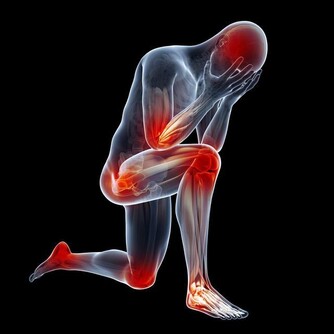

肺部是呼吸系統重要的器官,人們的輕鬆的呼吸、乾淨的血液都依靠肺部的運行。當肺部出現了健康問題,對於整個身體健康是有很大影響的,甚至會危及到生命,所以及時知曉肺部的求救信號是非常重要的。睡覺時有哪些異常情況是肺在求救呢?接下來讓我們一起來了解一下。

3、呼吸困難

肺部有疾病的人,首先影響的就是人的呼吸,呼吸對人的重要性恐怕不必再說,呼吸停止了,生命也會走向終結。肺部是呼吸系統重要的器官,肺出現問題,呼吸也會產生異常。當在晚上睡覺的時候,經常的胸悶氣短,甚至呼吸困難,讓人在睡夢中突然醒來,大喘幾口氣才會好轉,就非常有可能是肺部受損嚴重的表現。出現這種情況很有可能是睡眠呼吸暫停綜合症,為了弄清楚原因,還是去醫院檢查一下比較好。

肺部受損是一件比較重大的事,出現了肺部疾病也不要拖延,一定要及早治療,這樣才能把後果盡量的降到最低。